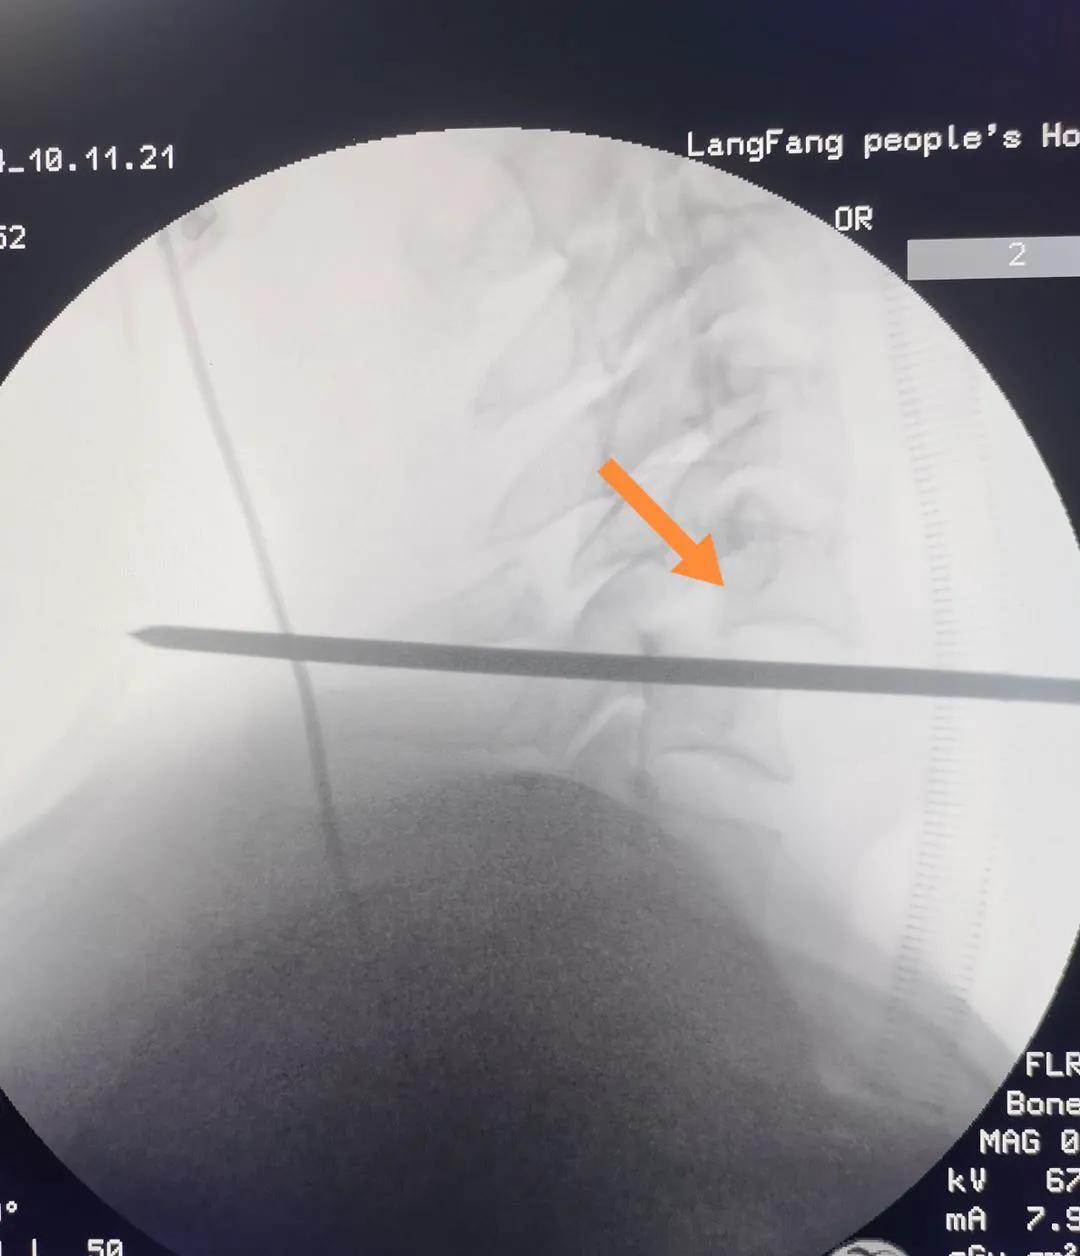

11月3日,某患者因头颈胸部外伤入院。经全面检查,诊断患者为“颈5骨折脱位,双侧关节突交锁、脊髓损伤”。患者入院后,康立星主任带领的骨一科专业团队高度重视,术前经过多次认真讨论,制定了科学周密的治疗方案。在手术麻醉科刘占波主任和马东风医生的通力配合下,康立星主任带领骨科医疗团队为患者施行“一期颈椎前后路联合骨折复位内固定术”。手术过程顺利,未输血,术中颈椎脱位完全复位,固定钢板螺钉位置良好,目前患者恢复良好。